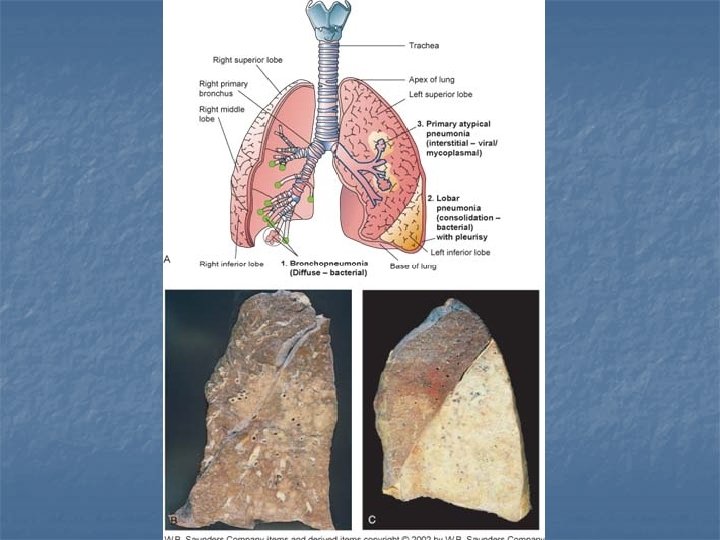

n Lobar pneumonia affects a lobe of the lungs (see x-ray), and bronchial pneumonia can affect patches throughout both lungs. Lobular pneumonia

TYPES OF PNEUMONIA LOBULAR BRONCHIAL